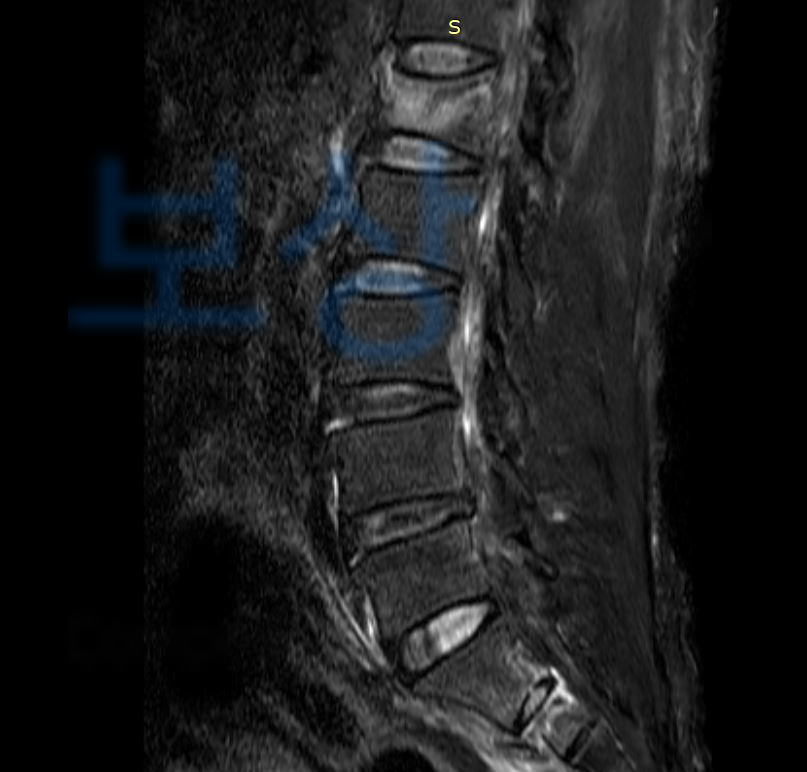

이 사고로 인해 이@@님은

우측 상,하치골가지골절 S32880

우측 천골익 골절 S3210

제 1요추부 3주 골절 S32090

진단을 받으셨고 골절의 모양이 좋지 않아 척추 후방고절술 즉 후방유합술을 받아 안정을 취하셔야 했습니다.

보상파트너는 이@@님의 영상CD를 함께 보며 보상의 범위가 어느정도 가능할지 기본적인 상담을 도와드렸고 상주하는 노무직원과 함께 장해급여 신청부터 지급까지 함께 진행하게 되었습니다